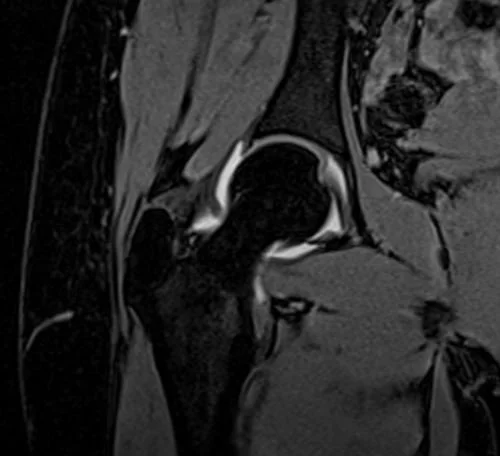

VIBE FAT SAT CORONAL POST JOINT INJECTION SEQUENCE USED IN HIP ARTHROGRAPHY IMAGING